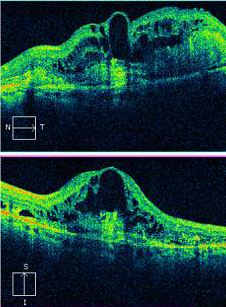

Optical coherence tomography/OCT

Optical coherence tomography (OCT) offers a noninvasive, high-resolution, optical cross-sectional method that utilized low-coherence interferometry.[68] OCT has become indispensable in the evaluation of patients with AMD. Imaging helps evaluate for tomographic sequelae of neovascular membranes, as well as monitor for treatment responses.

Type 1 CNVM= sub-RPE CNVM, usually related to occult CNVM on FFA

Type 2 CNVM= subretinal CNVM (superficial to the RPE), usually corresponds to classic membranes on FFA

Type 3 CNVM= retinal angiomatous proliferation (RAP)